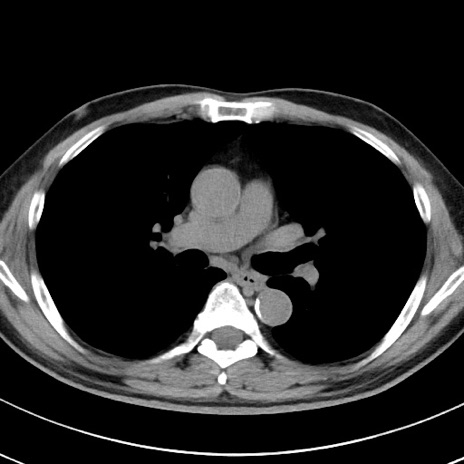

【腹部TIPS】症例29 参考症例 CT(横断像)

症例

70歳代男性